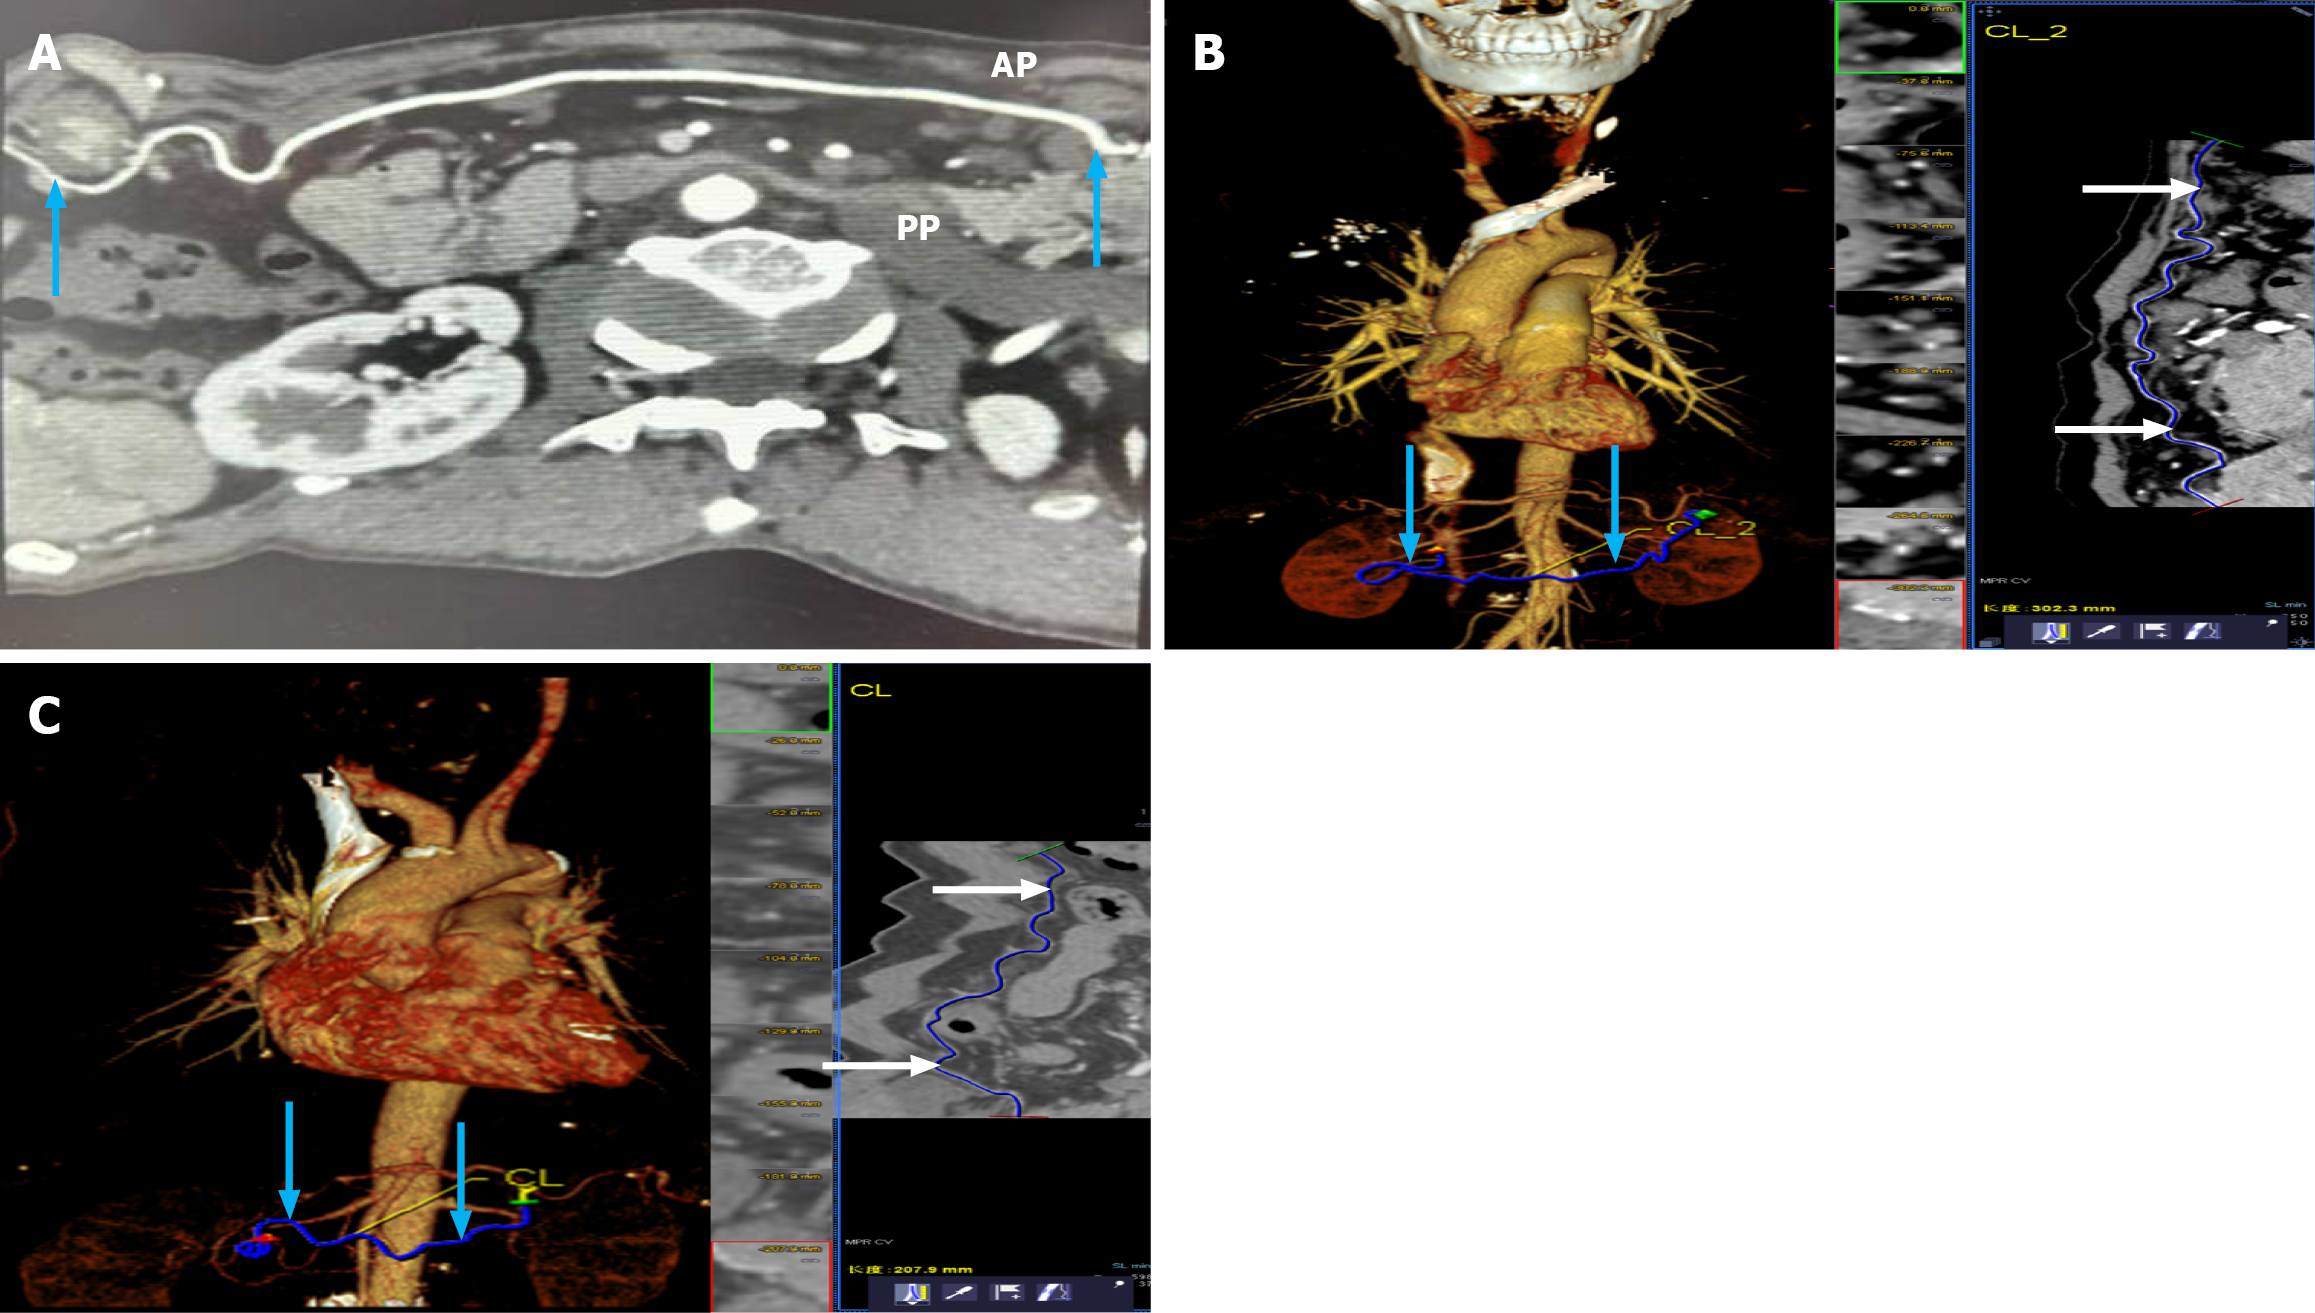

Measurements were performed along the arterial centerline using multiplanar reconstruction to accurately account for vessel curvature. Representative examples of measurement techniques for shorter and longer RGEAs, including two-dimensional CTA images, three-dimensional reconstructions, and integrated multiplanar views, are shown in Figure 2. Any interobserver measurement discrepancy greater than 2 mm was resolved through consensus.